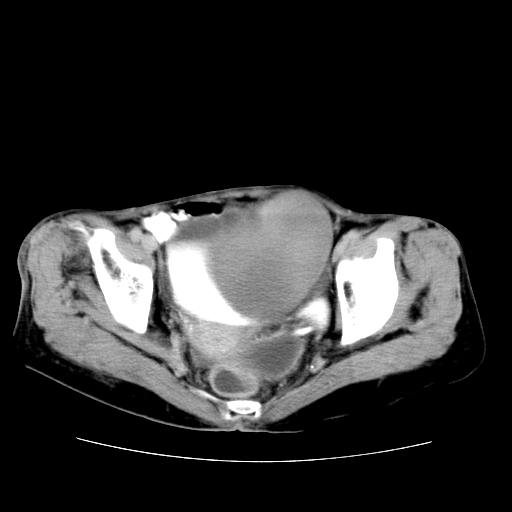

女性,72岁。

主诉下腹部坠痛不适1年余。

子宫增大如孕3月大小,质软,活动可,无压痛。

b超提示:盆腔(子宫前方)低回声团块。

临床诊断:盆腔肿块查。

1、这个肿瘤密度均匀,增强后轻中度均匀性强化,与左侧附件关系密切,肿瘤边缘光整、清晰。

2、左侧卵巢增大呈8×8×10cm大小,实性,表面光滑,边清,左侧输卵管爬行于左卵巢上,子宫萎缩。右输卵管、卵巢萎缩。

3、病理号:092658

左侧卵巢纤维瘤(性索间质肿瘤)

卵巢纤维瘤为良性卵巢性索间质肿瘤,常为单侧发病,当合并腹水或胸腹水时称麦格斯(meigs)综合征,肿瘤切除后胸腹水可消失。ct表现为盆腔内边界清楚的圆形或椭圆形肿块,常有分叶或不规则;肿瘤多为实性,少数为囊性、囊实性,完全囊性者可见壁结节。实性部分与子宫等密度;增强扫描常为轻度强化或几乎不强化。